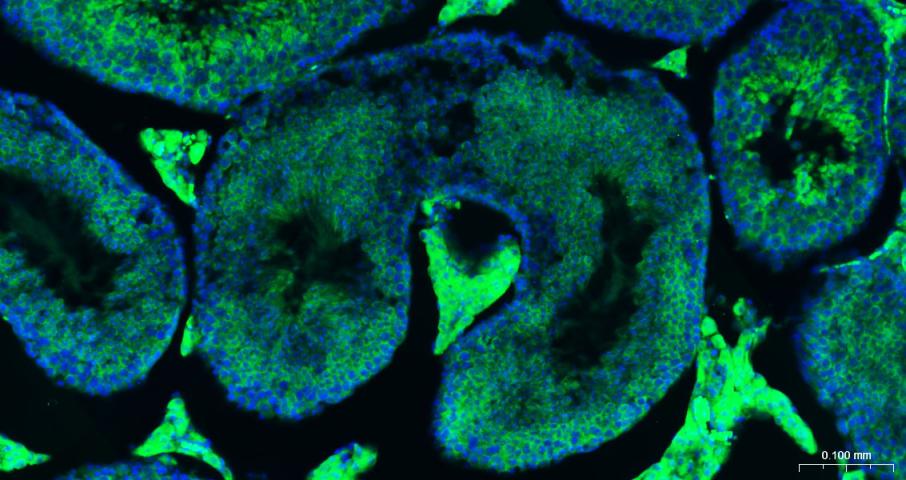

Paraformaldehyde-fixed, paraffin embedded Mouse Testicles; Antigen retrieval by boiling in sodium citrate buffer (pH6.0) for 15 min; Antibody incubation with eIF4E Monoclonal Antibody, Unconjugated (bsm-63259R) at 1:200 overnight at 4°C. Followed by conjugated Goat Anti-Rabbit IgG antibody (green, bs-0295G-BF488), DAPI (blue, C02-04002) was used to stain the cell nuclei.